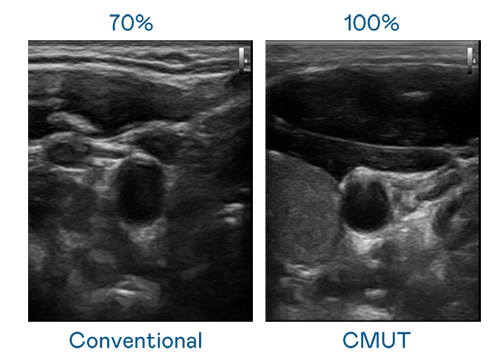

CMUT 技术是一种用电容式微机电元件来产生超音波讯号的技术。与传统 PZT 压电式技术相比,CMUT 频宽增加 30%,更宽频的超音波讯号让影像解析度大幅提升,是实现高影像品质医疗超音波扫描、促进精准医疗发展的关键技术。

大频宽带来超清晰影像

超音波影像的解析度高低,首先取决于探头能发出的讯号频宽。娃娃脸电影在线观看 CMUT 可提供高清晰的超音波讯号,提供高频宽、高灵敏度、影像纹理细节更高的超音波影像,协助医护人员缩短影像判读时间及利用精准的医疗影像进行诊断。